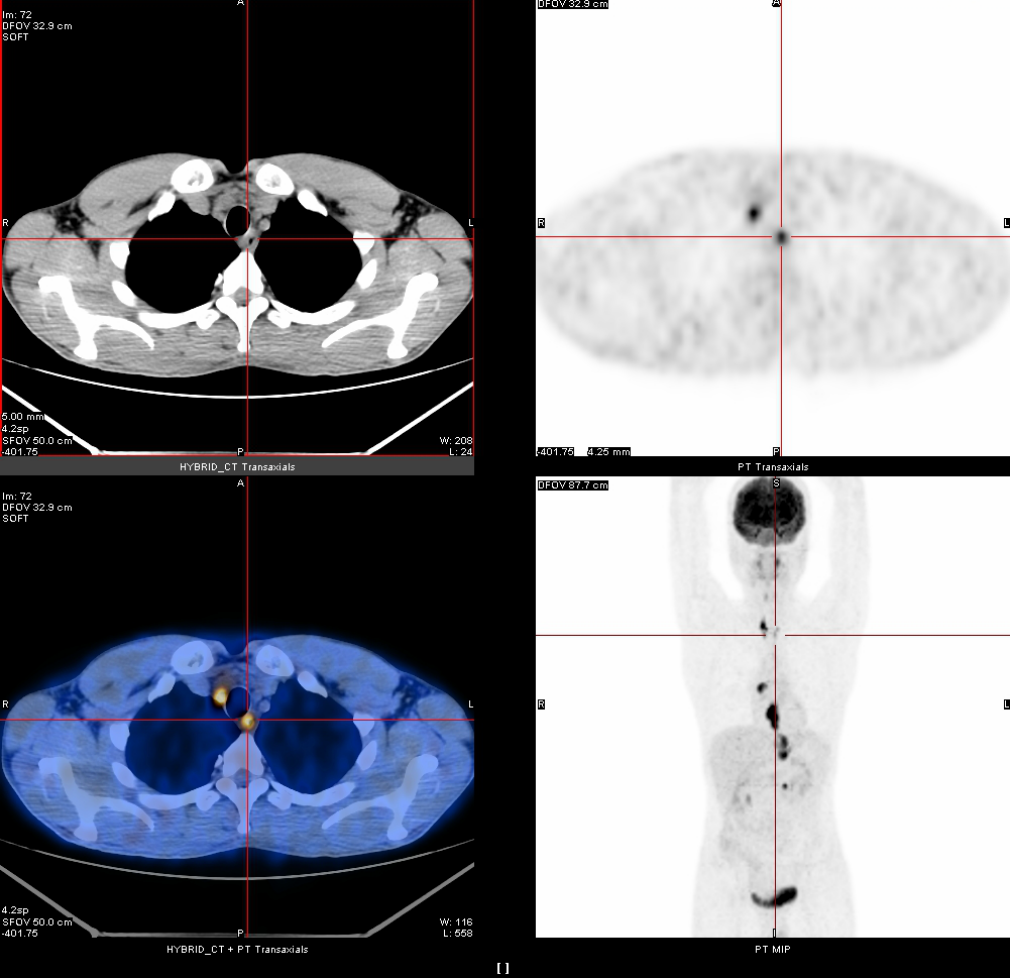

2020年3月13日

全身PET-CT示:1、食管胸中下段管壁不规则增厚,代谢增高,考虑食管癌。2、上纵隔胸廓入口区气管两旁、右下肺静脉后方、贲门区、肝胃间隙、降主动脉后方、膈肌脚后方、腹膜后腹主动脉左旁(左肾门下方平面)见多发高代谢肿大淋巴结,考虑淋巴结转移,建议随访复查。3、右肺上叶前段胸膜下小结节影,代谢未见增高,建议随访复查。4、右肺下叶外基底段条索影,考虑慢性炎性改变。5、双侧上颌窦轻度慢性炎症。6、双侧颈部多发小结节影,代谢未见增高,考虑淋巴结慢性炎性增生。7、肝左叶内侧段小钙化灶。